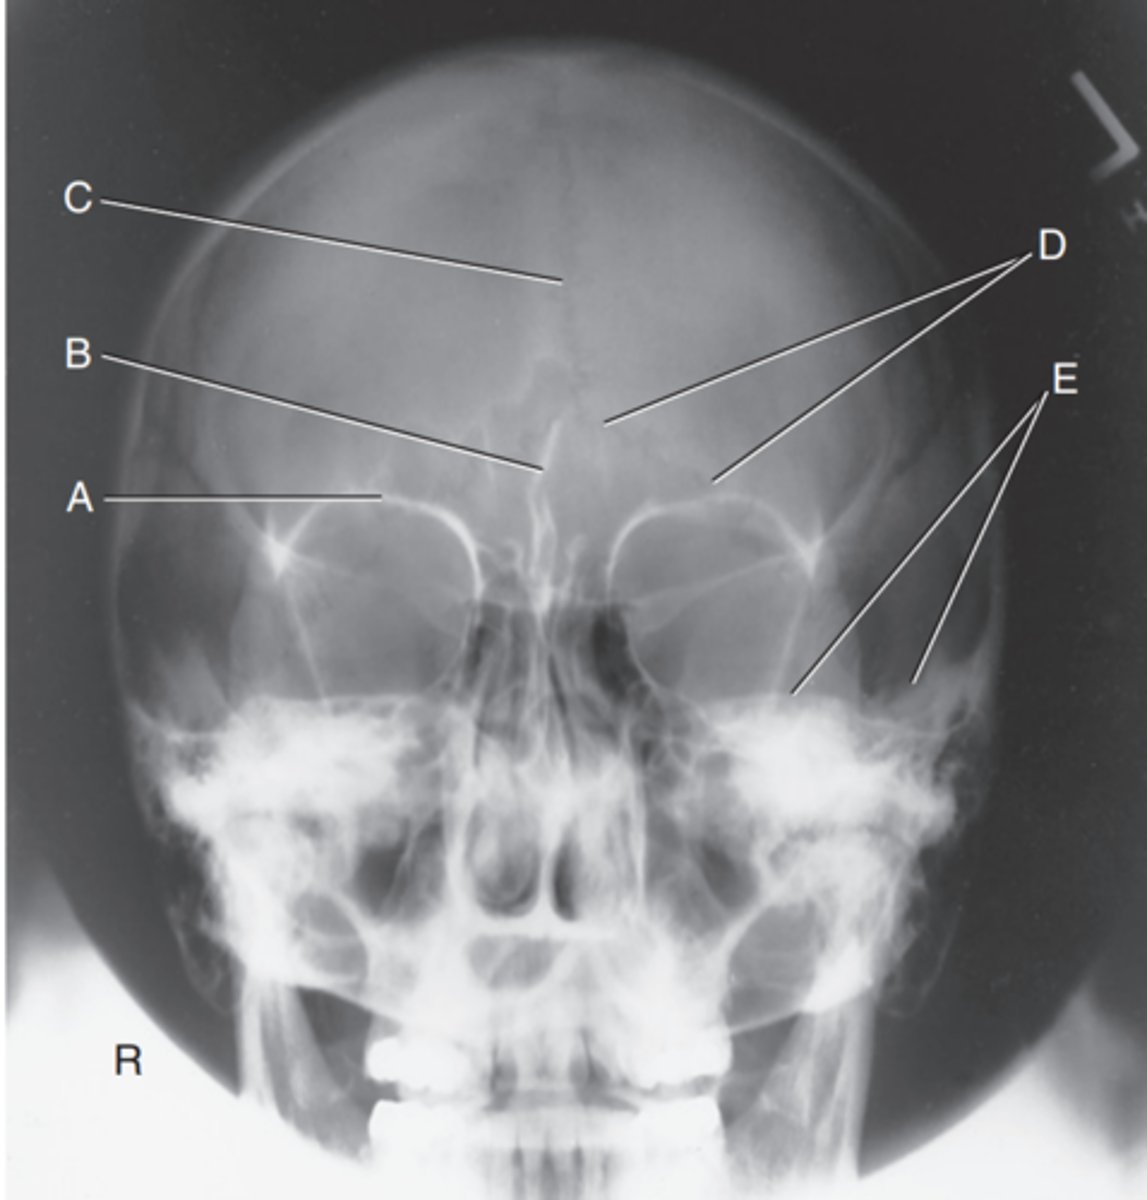

Dorsum sellae of sphenoid

Label A

Posterior clinoid processes

Label B

Petrous ridge or petrous pyramid

Label C

Parietal bone

Label D

Occipital bone

Label E

Foramen magnum

Label F